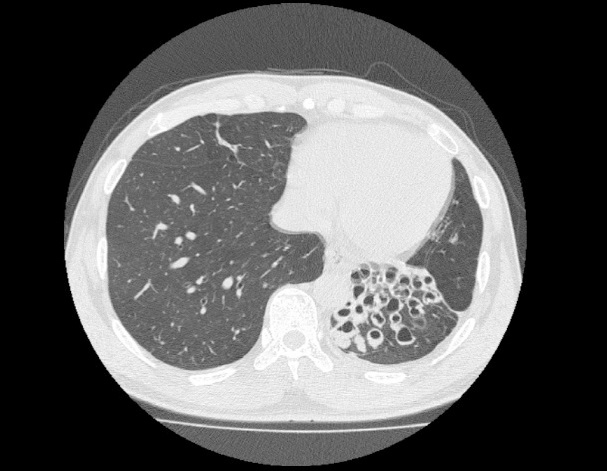

비결핵항산균에 감염된 폐사진